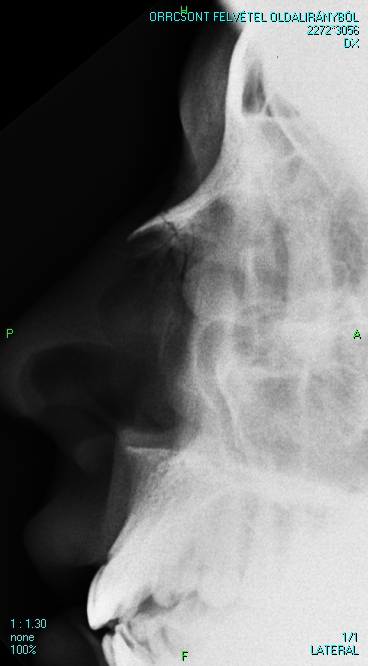

• For routine diagnosis of nasal bone fractures a radiogram is taken only from a lateral projection (PA radiograms have no value due to superimposed shadows of the cranial bones).

8.A young woman was assaulted. She had nose bleeds and a laceration at root of the nose.